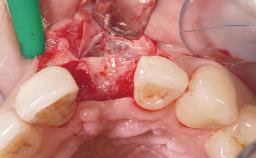

Immediate Flapless Placement of an Implant in a Maxillary Right Lateral Incisor Site

This 43-year-old male patient, a non-smoker, came to our practice because of a fracture of tooth 12 caused by a bicycle accident. Due to the combined para- and infrabony crown and root fracture, tooth extraction, and subsequent implant placement were suggested to the patient as the therapy of choice. The patient had high esthetic expectations with regard to the treatment outcome and asked for an immediate fixed provisional restoration. His individual esthetic risk profile summed up to a medium esthetic risk.

Placement Protocol Immediate implant placement

Tooth Site Maxillary incisor or canine

Socket Morphology Single-root socket

Socket Integrity Sufficient, with intact bone walls

Loading Protocol Immediate